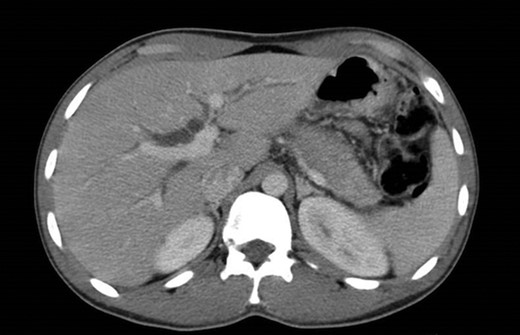

Laboratory tests including IgG4, anti-smooth muscle antibody (ASMA), anti-mitochondrial antibody (AMA), anti-nuclear antibody (ANA), anti-neutrophil cytoplasmic antibody (ANCA), anti-Sjogren’s-syndrome-related antigen A/B, anti-Smith (anti-Sm), anti-dsDNA, complement C3/C4, CEA and CA 19-9 were all negative. Endoscopic ultrasound (EUS) revealed a heterogeneous parenchyma of the pancreatic head and an EUS-FNA was performed. The MRCP, on the other hand, suggested the existence of a distal cholangiocarcinoma, because of the sudden typical stenosis in the distal CBD with a general dilatation of the upper bile ducts (Fig. 3). Unfortunately, the biopsy was not enough to establish a definitive diagnosis.

ERCP. Heterogeneous pancreatic parenchyma and pseudonodular appearance of the pancreatic head. Wirsung duct with no stenosis or obstructions. Common bile duct with normal caliber until the intrapancreatic portion where a highly suspicious of malignancy 2 cm irregular stenosis is seen.